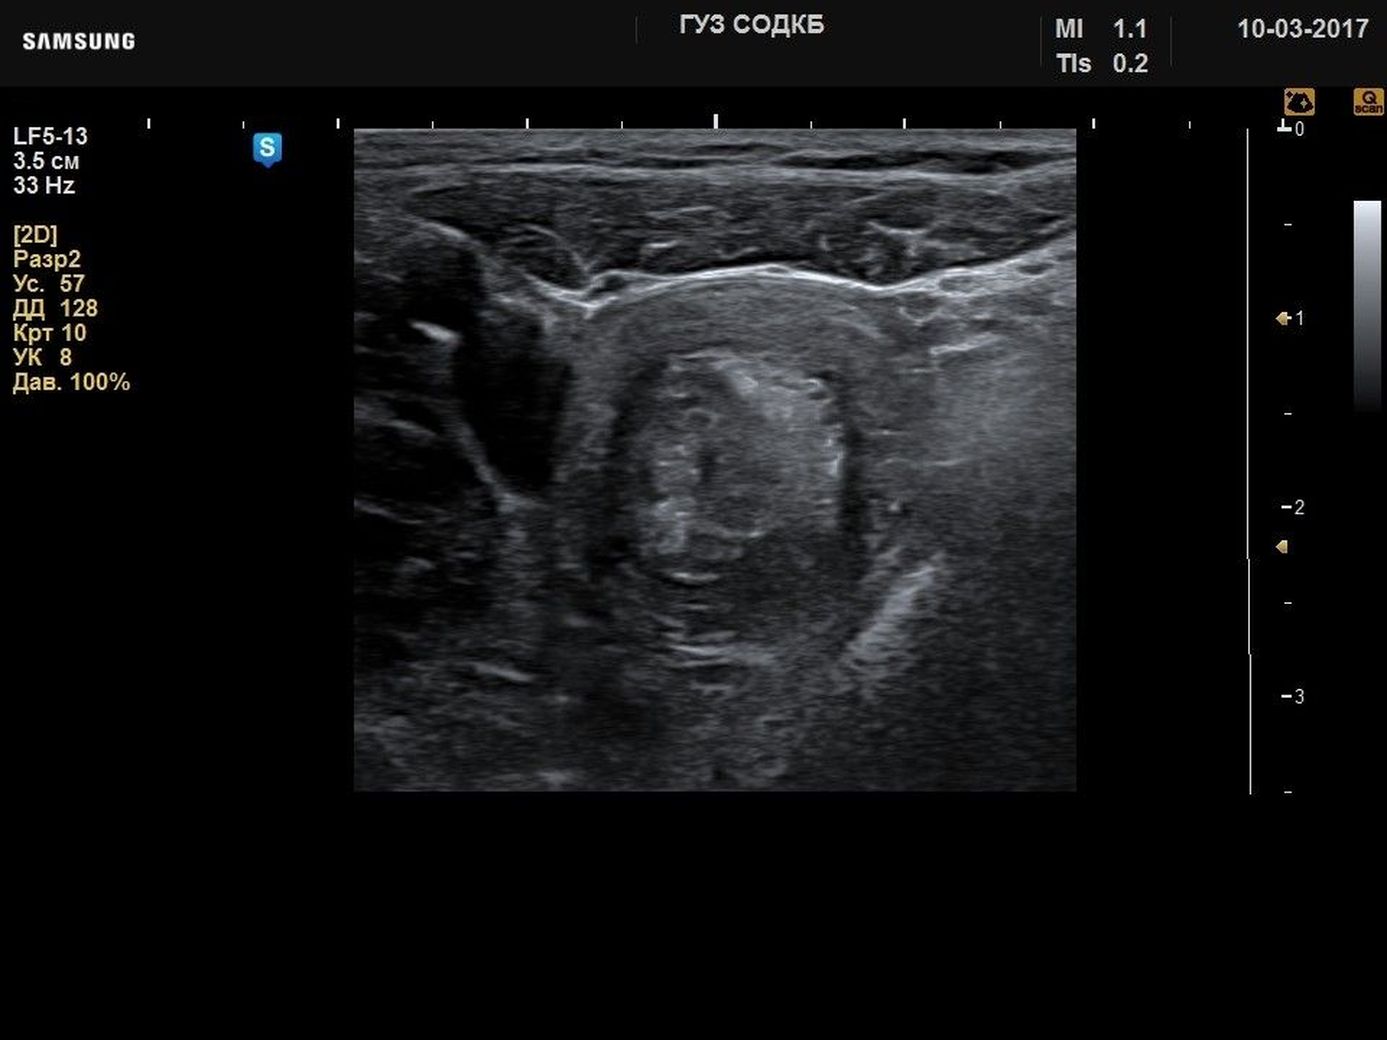

Cancer uz

Узи кишков 87 фотографий